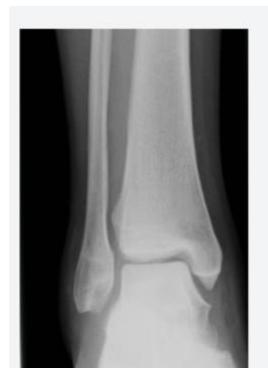

Ankle Views

- Mortise view:

- c. anterior posterior with 15 degree internal rotation

Normal vs Abnormal Comparison

- What is shown, indicate what?

- b. Normal